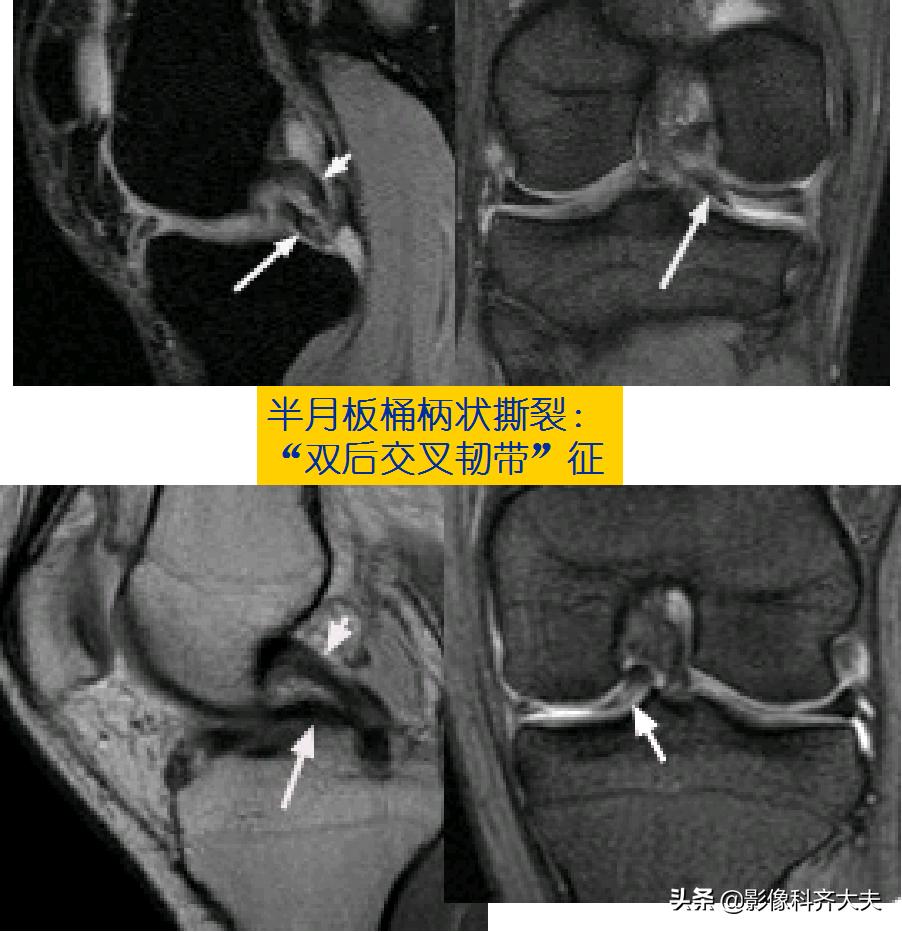

桶柄状撕裂示意图

半月板撕裂后移位